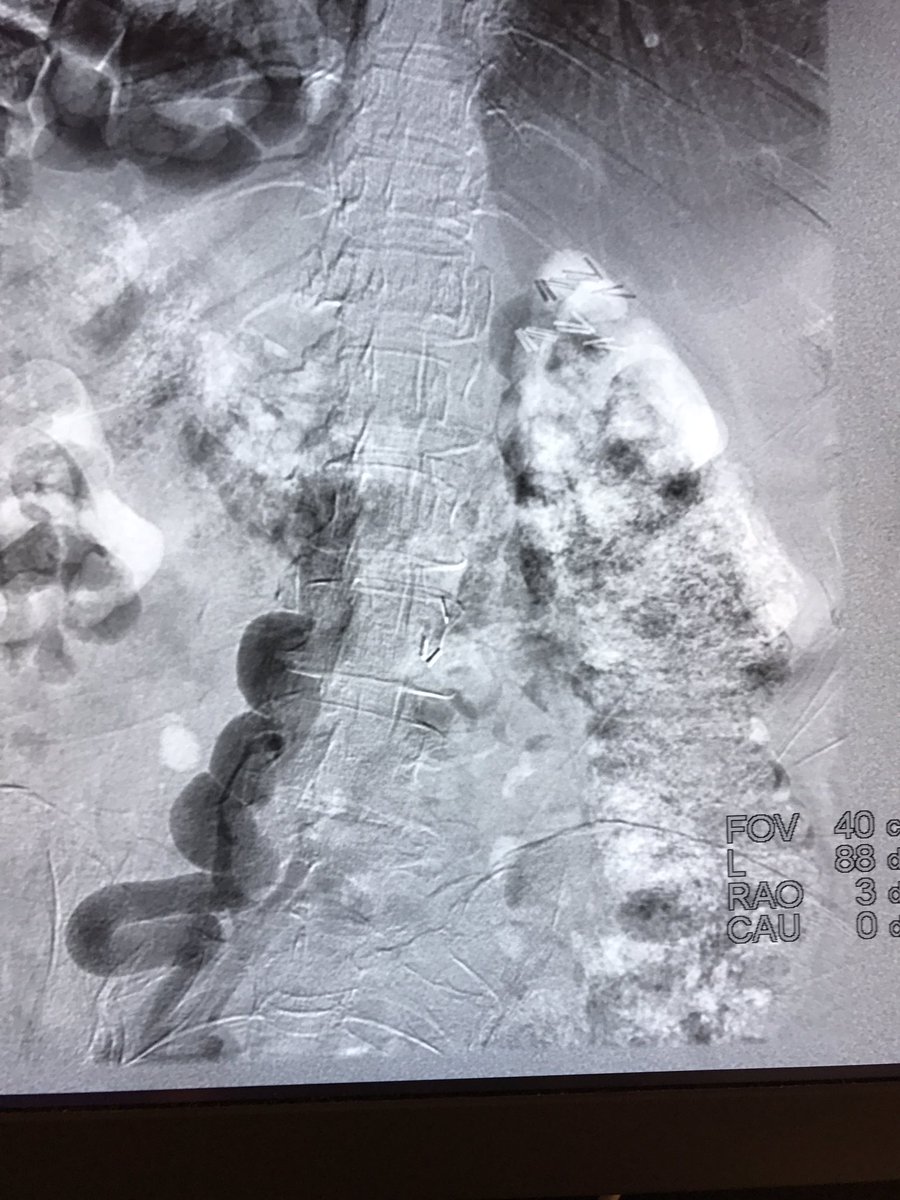

It was hard to say goodbye to this 4 year old filter with strut in the aorta | #iRad #radres #IRmusicvideos #FOAMed #Boyz2men #IRonc